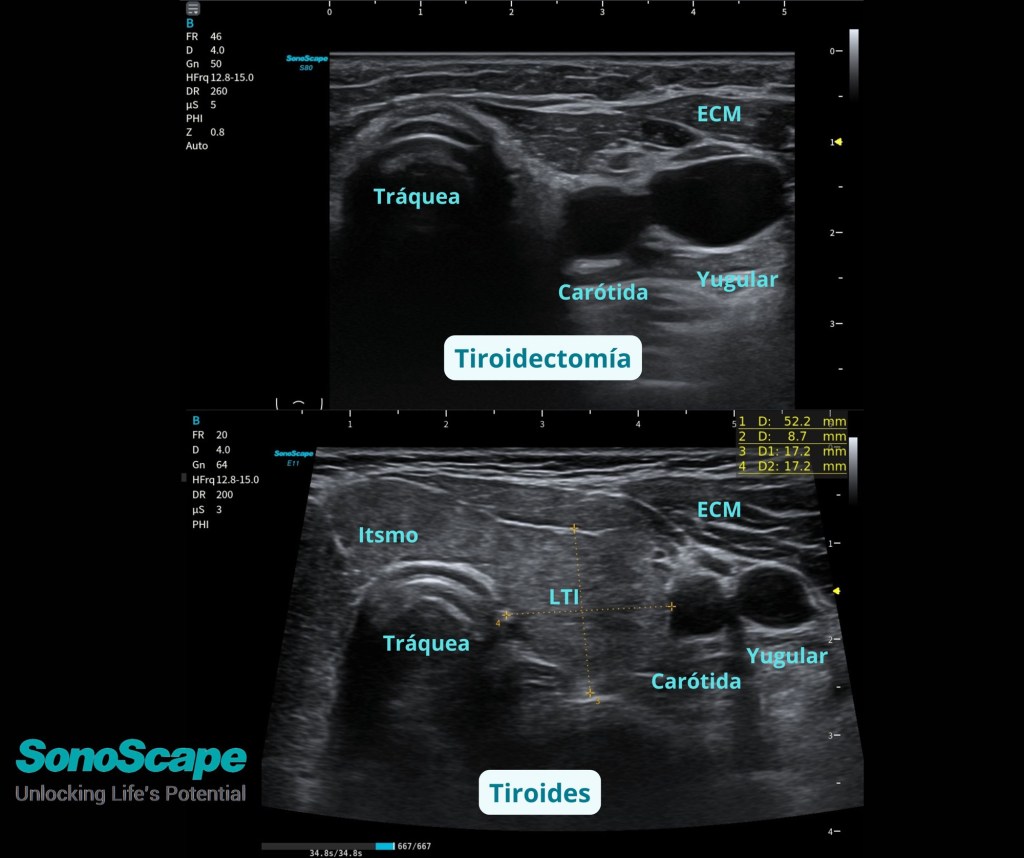

Fotos:

IMAGENES PROPIEDAD DEL BLOG ecografiafacil.com no está autorizada la copia sin consentimiento.

Imágenes del Portatil E11 de SONOSCAPE. https://sonoscapespain.es/producto/sonoscape-x11-e11/ (info producto)